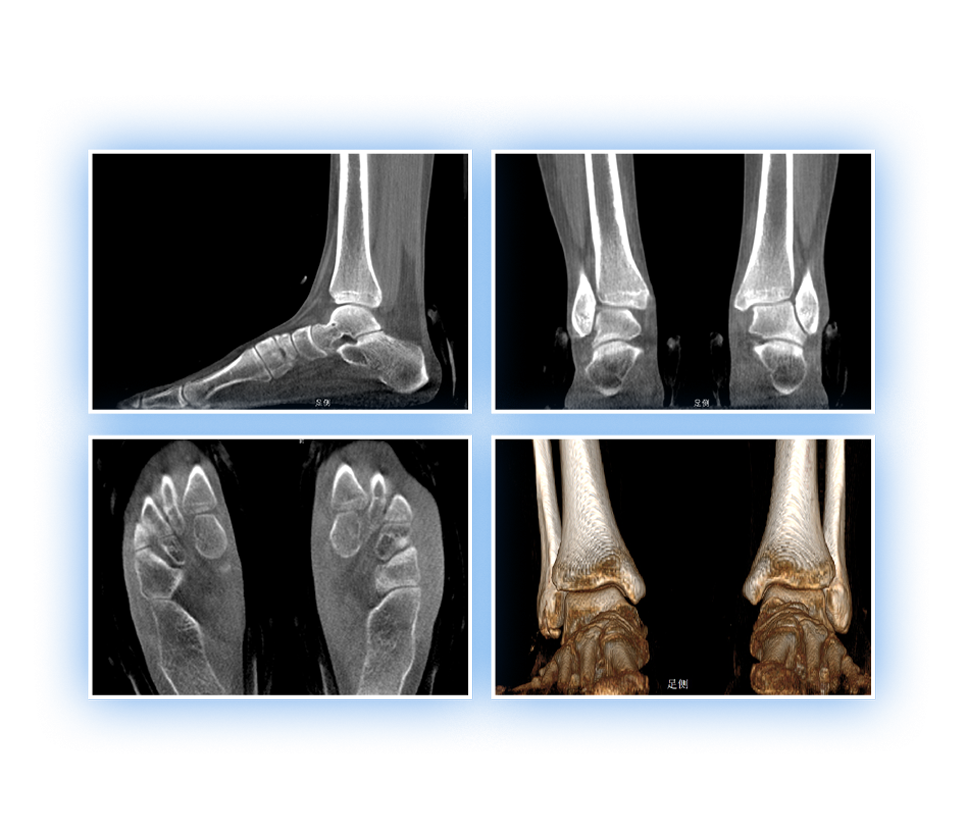

足踝

VR体绘制重建